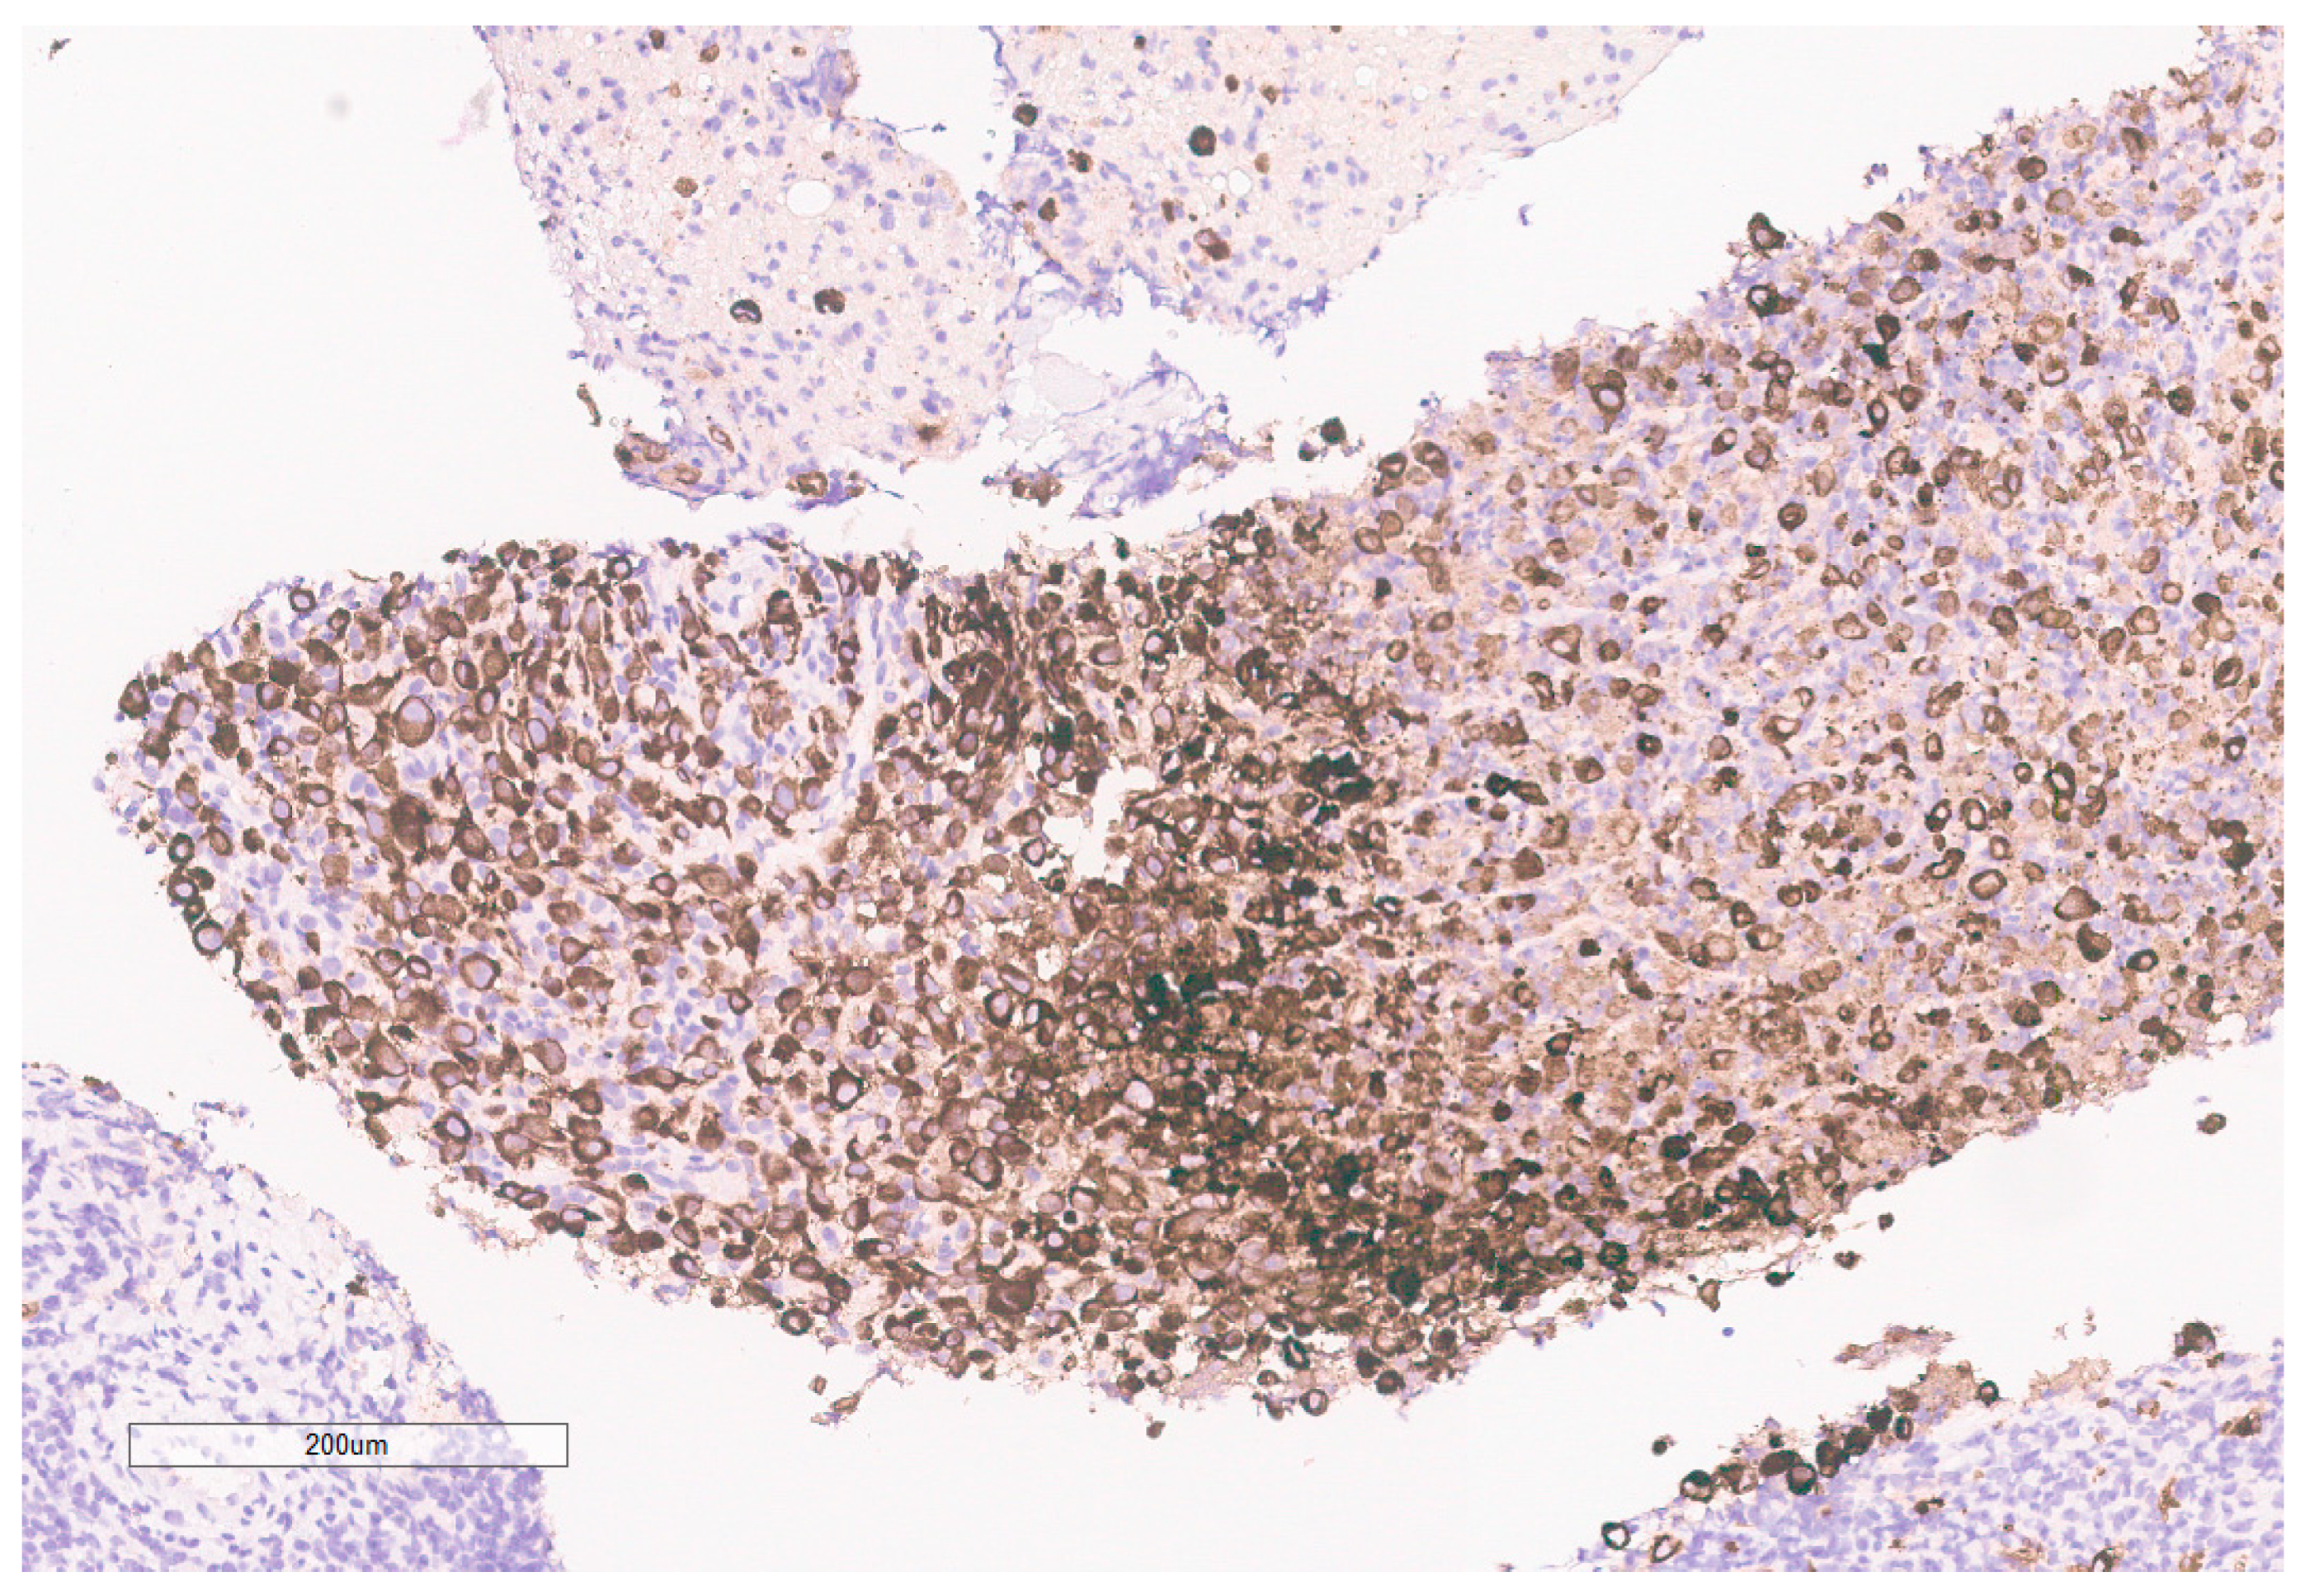

The biopsy of right kidney demonstrated mostly fibrinous material with small fragments of renal parenchyma with interstitial chronic inflammation and no definite tumor. The biopsy of a retroperitoneal lymph node showed high grade tumor composed of discohesive rhabdoid cells with highly atypical nuclei and eosinophilic cytoplasm involving lymphoid tissue with areas of necrosis and neutrophilic inflammation with necrosis and limited viable tumor cells (Figure 7). By immunohistochemistry, the cells were positive for pankeratin (Figure 8) and PAX8 (Figure 9) and negative for CK7, CK20, GATA3, CDX2, TTF1, CAIX, ERG, S100, CD34, CD30, SMA, desmin, OCT3/4 and CD163. The tumor cells showed diffuse loss of SMARCB1/INI-1 (Figure 10). The INI-1 was reviewed by several experienced pathologists that interpreted the stain as negative. While there is some background cytoplasmic and nuclear staining in the entire specimen, the norm is to compare staining with the adjacent internal positive control. Given that, in this case, the lymphocytes stained strongly positive for INI-1, it was appropriate to interpret this is as a negative stain in this context. As evidenced by the high-power image, the staining appears to be of a background variety and limited to the cytoplasm, in which the nuclei remain negative. Hence, this is interpreted as a negative stain.

Figure 9. PAX8 is positive in the tumor.